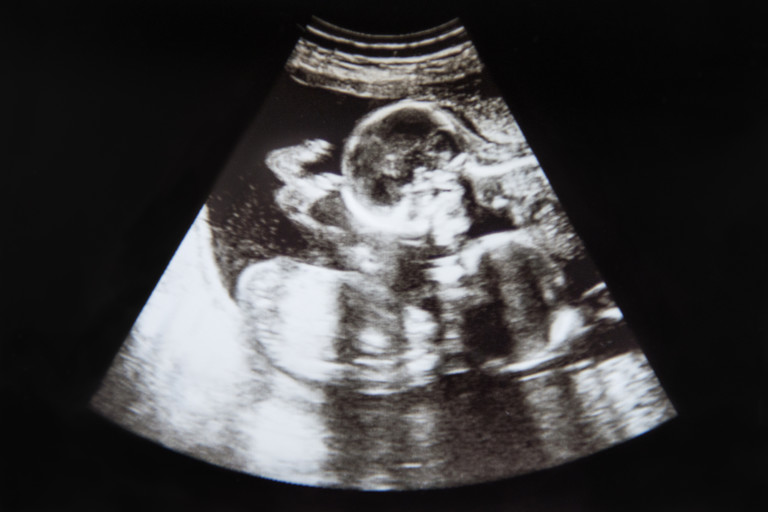

Много вероятно е явлението да бъде възприето като аномалия от лекаря, тъй като той измерва големината на ембриона, за да разбере неговата възраст. При наличието на два ембриона с голяма разлика в размера, лекарят е по-вероятно да помисли, че при по-малкия има някаква аномалия. Това може да се случи в много ранните етапи на бременността при изследване с ултразвук.